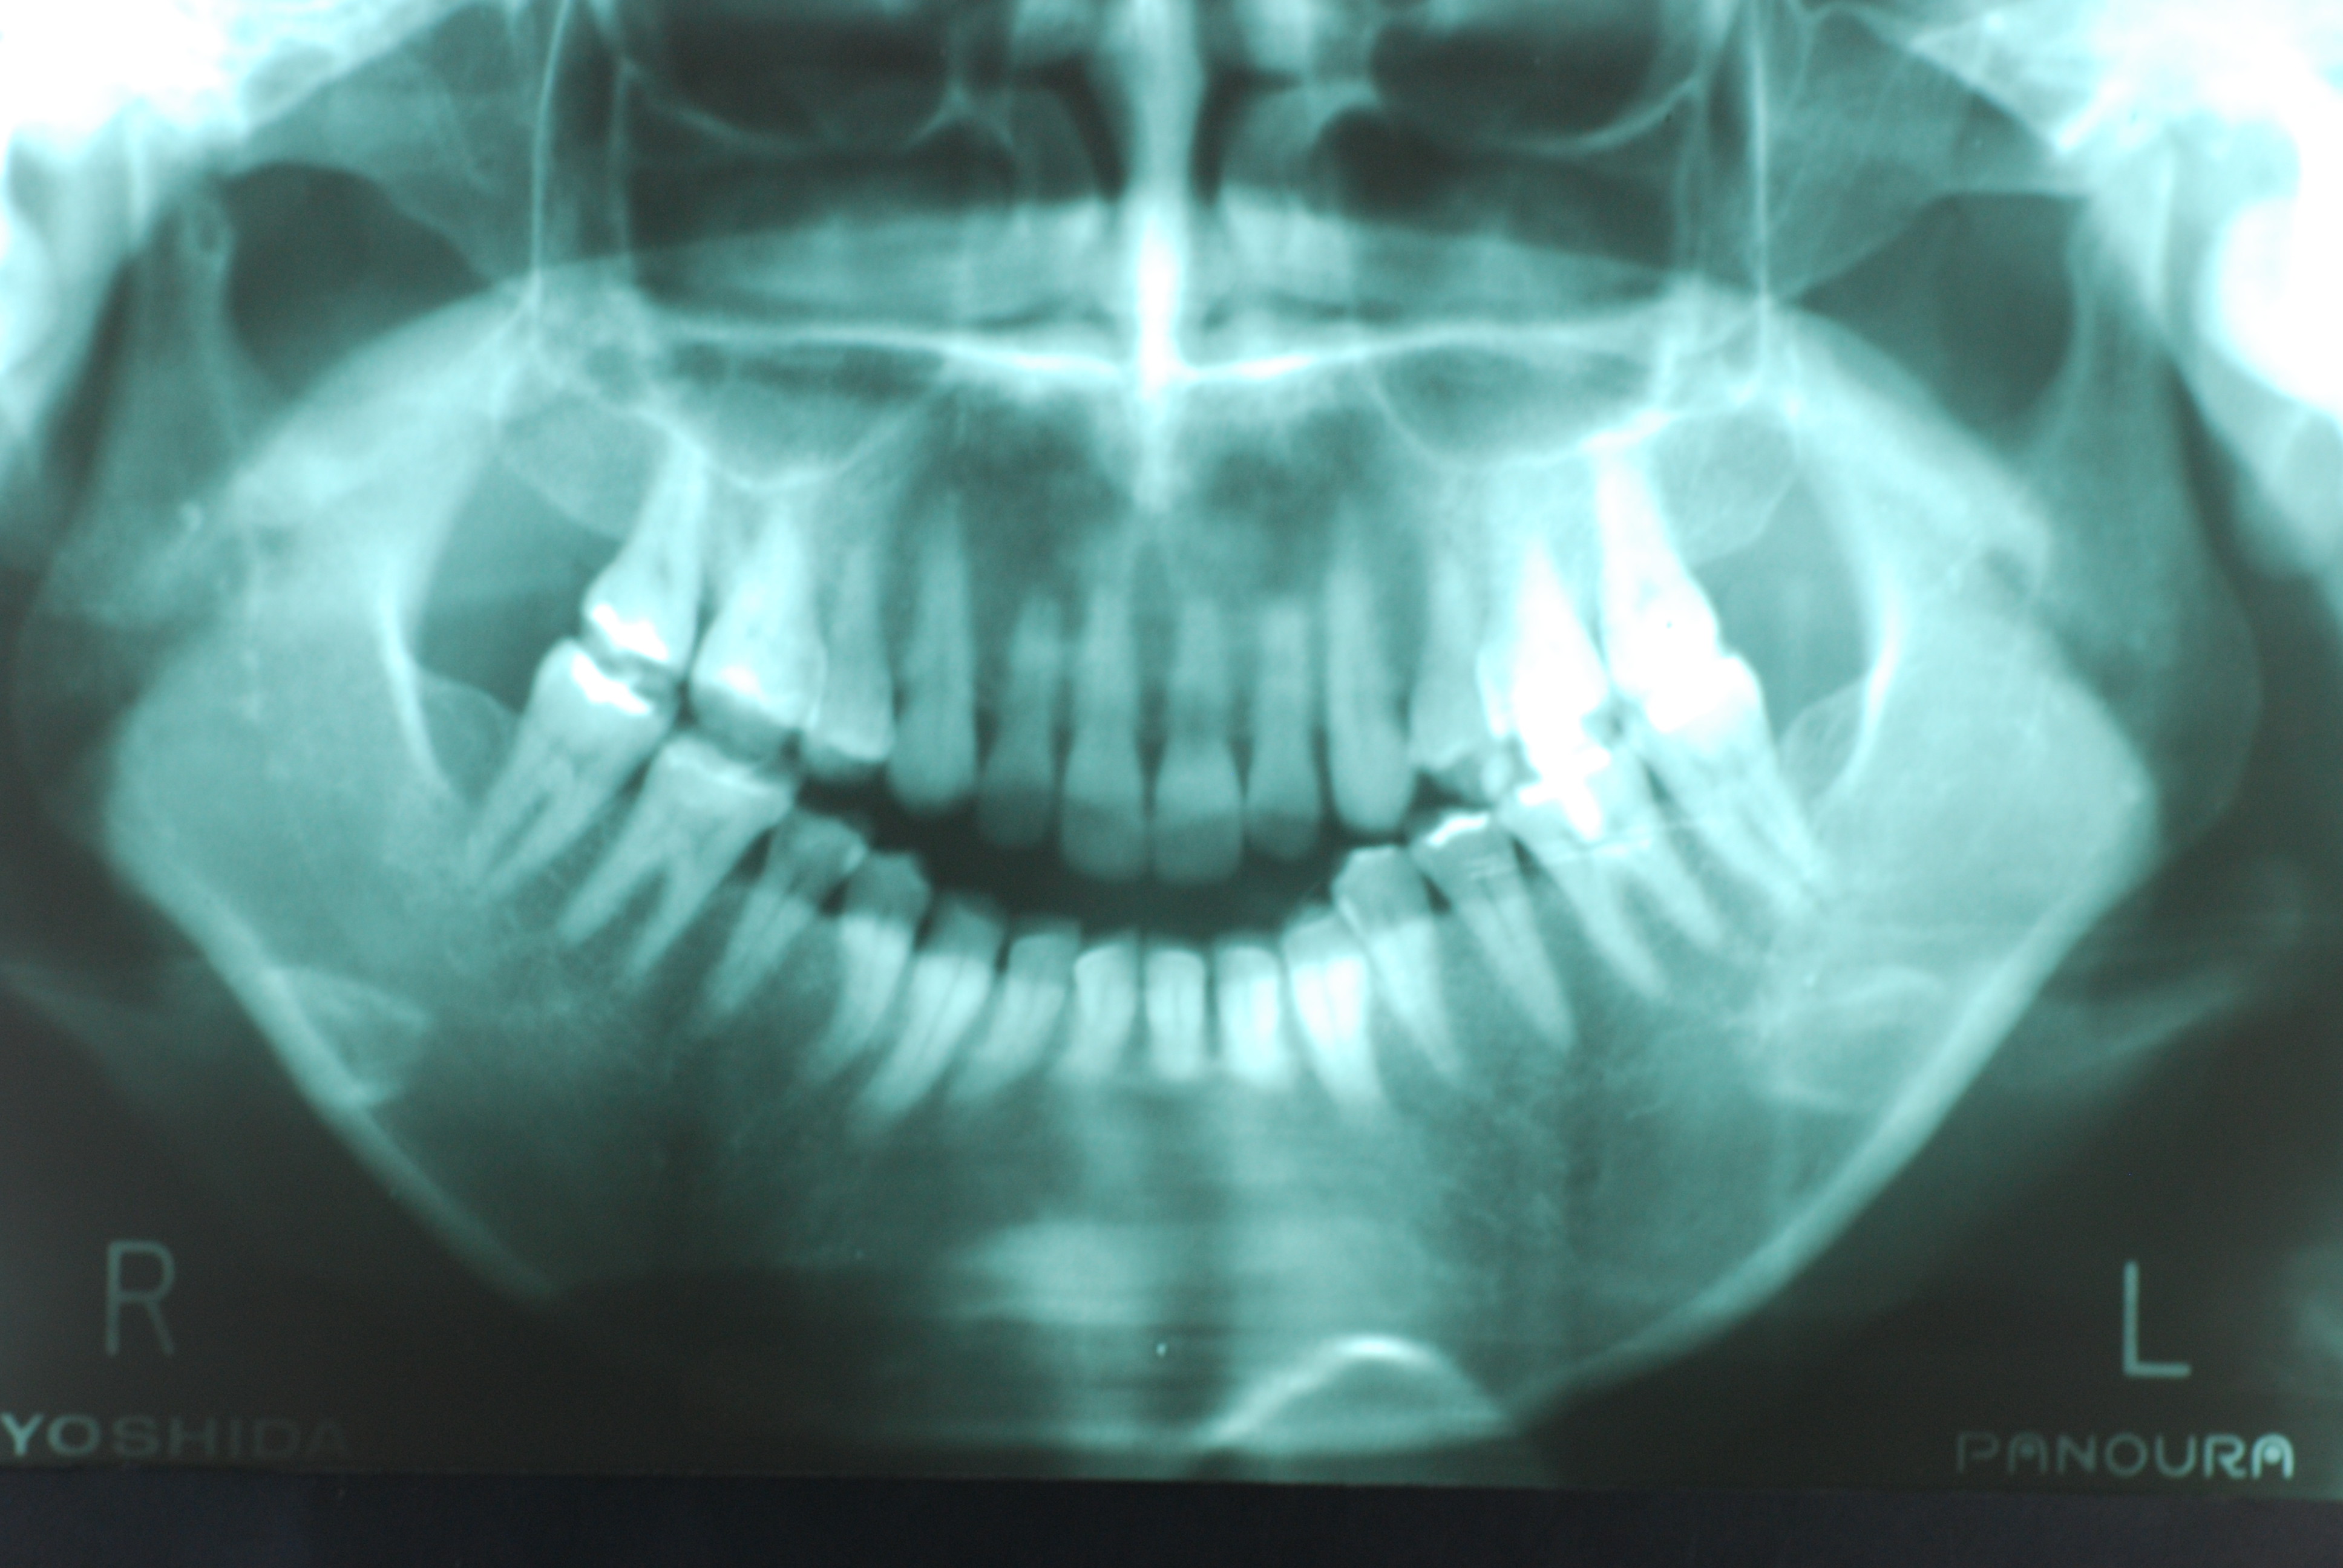

現実を見ればお口の中には“異物”である金歯、銀歯、セラミック、インプラントのオンパレードです。

これ等のものは、異物です。無い方が病気にならず健康でいられるのです。

必ずばい菌が侵入しないようにしてばい菌である虫歯を除去します。

銀歯の下はばい菌だらけです。こういうのはよくあります。取り残しですね。![treatment_05[1]](https://livedoor.blogimg.jp/netdental/imgs/3/a/3ad019d0-s.jpg)